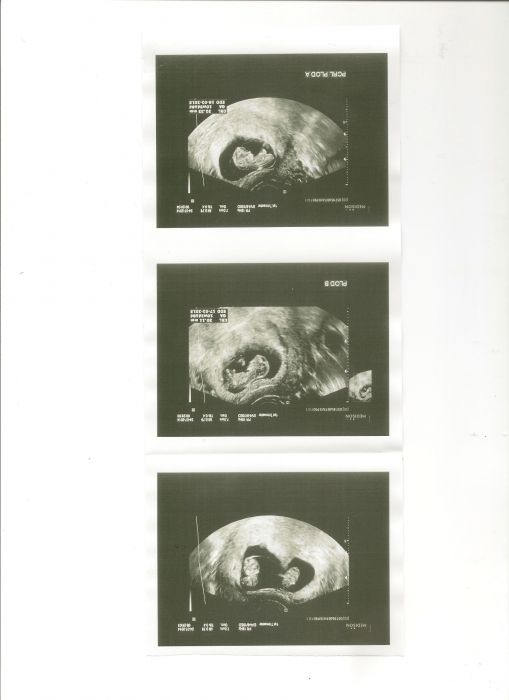

) no mě nikdy nic nebylo a není a rovnou tloustnu (at jím, nebo ne ). No co se dá dělat...ale kontrola minulý týden ve čtvrtek proběhla a obě mimi tam jsou a v pátek jdu na prvotrimestrální screening, tak jsem zvědavá... mám ze čtvrtka fotečky, tak je sem zkusím přihodit... a jinak tu máte super fotky...jak svatební civilní i vašich robátek